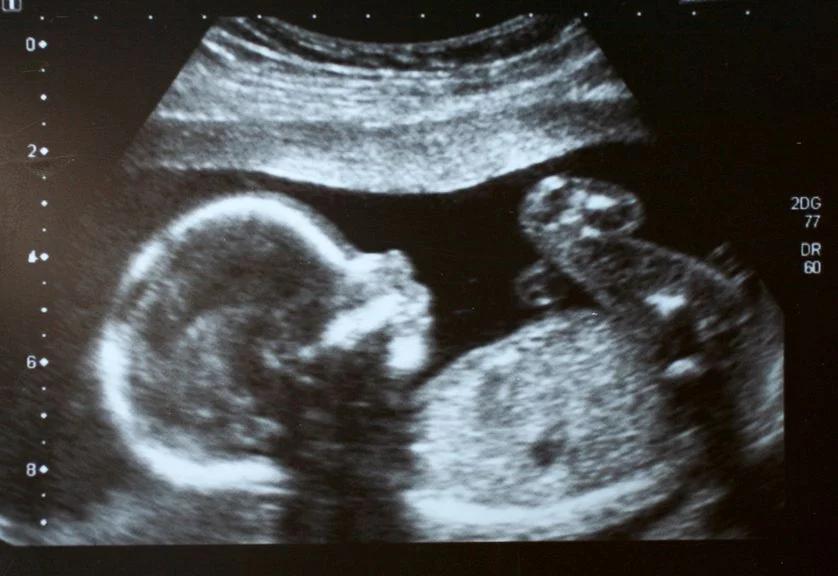

Was ist ein großer Ultraschall?

Ein großer Ultraschall, auch als fetale Ultraschalluntersuchung bezeichnet, ist eine bildgebende Untersuchung, die mithilfe von Schallwellen ein detailliertes Bild deines Babys im Mutterleib erzeugt. Der Ultraschall ist ein sicheres und schmerzloses Verfahren, das keine schädlichen Strahlen verwendet. Er spielt eine wichtige Rolle in der Schwangerschaftsvorsorge und ermöglicht es den Ärzten, die Entwicklung deines Babys genau zu beobachten und eventuelle Auffälligkeiten frühzeitig zu erkennen.

Was passiert beim großen Ultraschall?

Der große Ultraschall wird in der Regel von deinem Frauenarzt durchgeführt. Bei der ersten Untersuchung wird der Ultraschall noch vaginal durchgeführt, bei den späteren Untersuchungen wird ein Gel auf deinen Bauch aufgetragen, um die Schallwellen besser durch die Haut leiten zu können.

- Die Untersuchung: Der Frauenarzt wird den Ultraschallkopf auf deinen Bauch oder in die Scheide legen. Während der Untersuchung wird er verschiedene Bilder deines Babys aufnehmen und diese auf dem Bildschirm des Ultraschallgeräts betrachten.